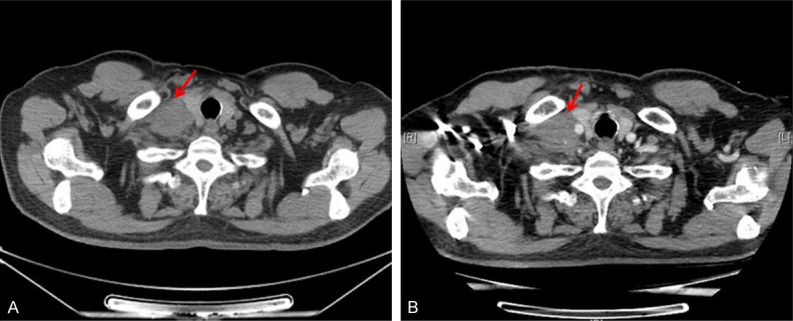

On October 23, 2020 and November 13, 2020, the patient was administrated with 2 cycle of PC regimen chemotherapy (Pemetrexed 500 mg/m2 and Carboplatin AUC = 5) with the consent from the patient. After the 2-month follow-up, the lesions achieved disease progression (PD) by Response Evaluation Criteria In Solid Tumors (RECIST) (version 1.1). Maximum diameter of cervical lymph nodes enlarged from 3.7 cm to 4.6 cm (Figure 2). On Dec 5, 2020, the patient was administrated with the first cycle of TP regimen chemotherapy (Albumin paclitaxel 260 mg/m2 day 1 and Cisplatin 75 mg/m2 day 1). Shortly, the patient received elective node irradiation (ENI) from Dec 21, 2020 to Feb 12, 2021 (Figure 3). Intensity modulated radiotherapy (IMRT) was adopted as the technique. Gross target volume (GTV) included the primary tumor located in the upper lobe of right lung, the metastatic tumor at the same lobe, and all the lymph nodes in the cervical and mediastinal region. The clinical target volume (CTV) covered all the GTV and the lymph node regions with observable metastatic lymph nodes, including supraclavicular, 2R, 4R, 4L, and subcarinal regions. The planning target volume (PTV) was defined as the CTV plus 0.5 cm margins (Figure 3). The total dose of PTV was 4785 cGy/29 f, and the dose of GTV was up to 5800 cGy/29 f using simultaneous integrated boost (SIB) technique. Dose constraints for normal tissues were required as follows: maximum dose for spinal cord should be less than 45 Gy; the mean lung dose was less than 12 Gy, and less than 25% of the lung volume received 20 Gy (V20<25%); and the mean cardiac dose was less than 30 Gy, with V30<40% and V40<30%. Sequentially, the patient received the second to the sixth cycles of TP regimen chemotherapy from Feb 18, 2021 to June 14, 2021. The assessment on July 1, 2021 was partial response (PR) after sCRT.

Figure 2.

Radiological appraisal of the right cervical lymph node lesion progressed after 2 cycles of chemotherapy. A. Baseline before therapy. B. After 2 cycles of chemotherapy.